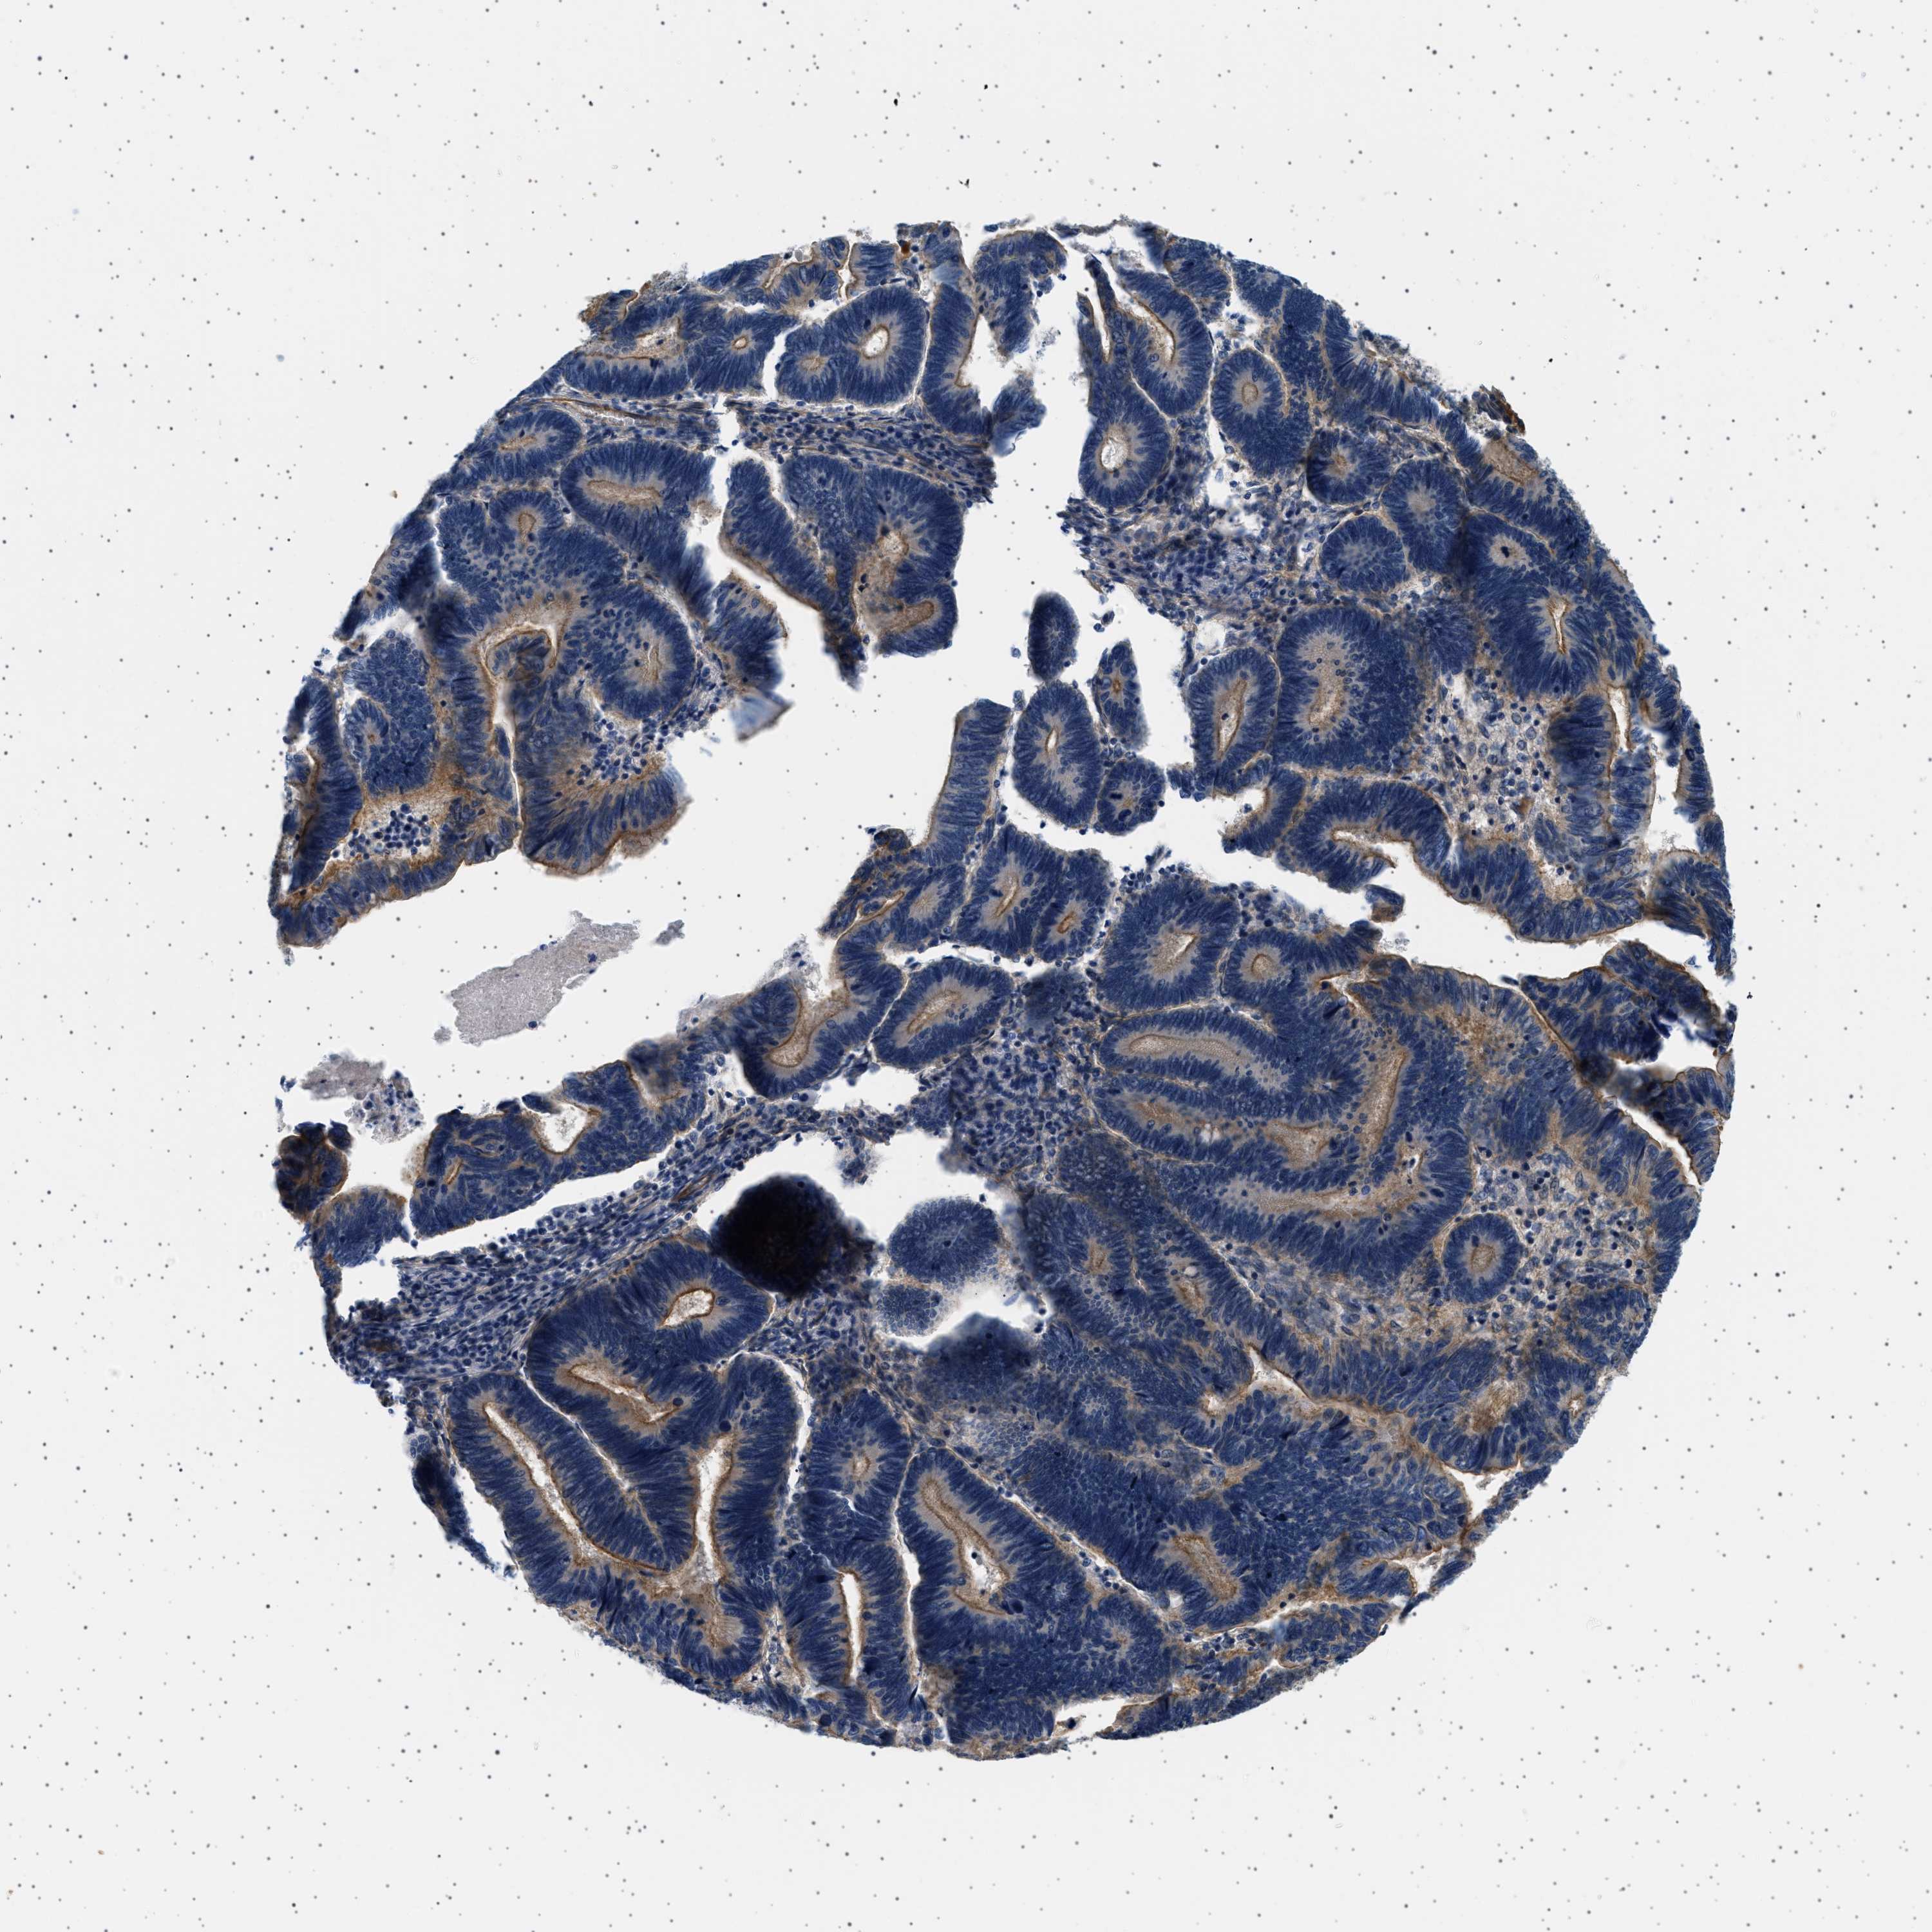

PANCREATIC CANCER - Protein expressioni

A mouse-over function shows sample information and annotation data. Click on an image to view it in a full screen mode. Samples can be filtered based on level of antibody staining by selecting one or several of the following categories: high, medium, low and not detected. The assay and annotation is described here.

Note that samples used for immunohistochemistry by the Human Protein Atlas do not correspond to samples in the TCGA dataset.

Antibody stainingi

Antibody staining in the annotated cell types in the current human tissue is reported as not detected, low, medium, or high, based on conventional immunohistochemistry profiling in selected tissues. This score is based on the combination of the staining intensity and fraction of stained cells.

Each image is clickable and will lead to virtual microscopy that enables deeper exploration of all samples and also displays staining intensity scores, fraction scores and subcellular localization as well as patient and tissue information for each sample.

Antibody HPA018096

Staining

High

Medium

Low

Not detected

Intensity

Strong

Moderate

Weak

Negative

Quantity

>75%

75%-25%

<25%

None

Location

Nuclear

Cytoplasmic/membranous

Cytoplasmic/membranous,nuclear

Adenocarcinoma, NOS